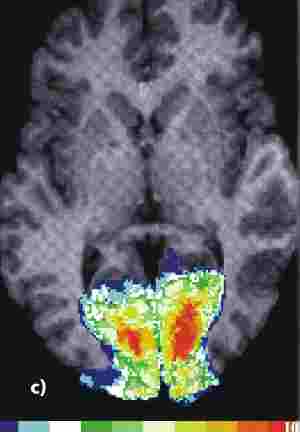

Sowohl im linken als auch im rechten Bild werden sehr unterschiedliche Arten von Daten miteinander kombiniert. Das NMR- Bild ist eine Art Photo einer einzelnen Gehirnebene - im allgemeinen die Darstellung einer typischen Hirnstruktur. Die funktionellen Messungen hingegen sind Resultate komplizierter Datenverarbeitung. Messungen vieler Einzelbilder werden gemittelt, gelegentlich auch Bilder, die von mehreren Menschen stammen. Messungen vor und nach einem Stimulus werden voneinander subtrahiert, so daß Differenzbilder entstehen. Diese gemittelten Differenzbilder werden einer genauen statistischen Analyse unterworfen: Wo sind statistisch signifikante Unterschiede zwischen der Kontrollmessung und der Messung während des Stimulus auszumachen? Die Signale sind oft äußerst schwach und müssen mit erheblichem Rechenaufwand gesucht werden. Zur graphischen Verdeutlichung dient die Falschfarbendarstellung, mit der auch die kleinste Änderung als blau-zu-rot-Signal dargestellt werden kann.

Die funktionellen Daten (bunt) in den beiden Bildern unten wurden mit der funktionellen Kernspintomographie (fNMR) gewonnen, bei der man Änderungen des NMR-Signals bei zunehmender Durchblutung eines aktiven Hirnareals auswertet. Als Beispiele für die Kombination von Bildern sind Überlagerungen von fNMR-Daten mit einem Kernspintomogramm (links) und mit einer graphischen Darstellung des Gehirns (rechts) abgebildet.

Aus: Forschen in Jülich, 1/2000, Forschungszentrum Jülich